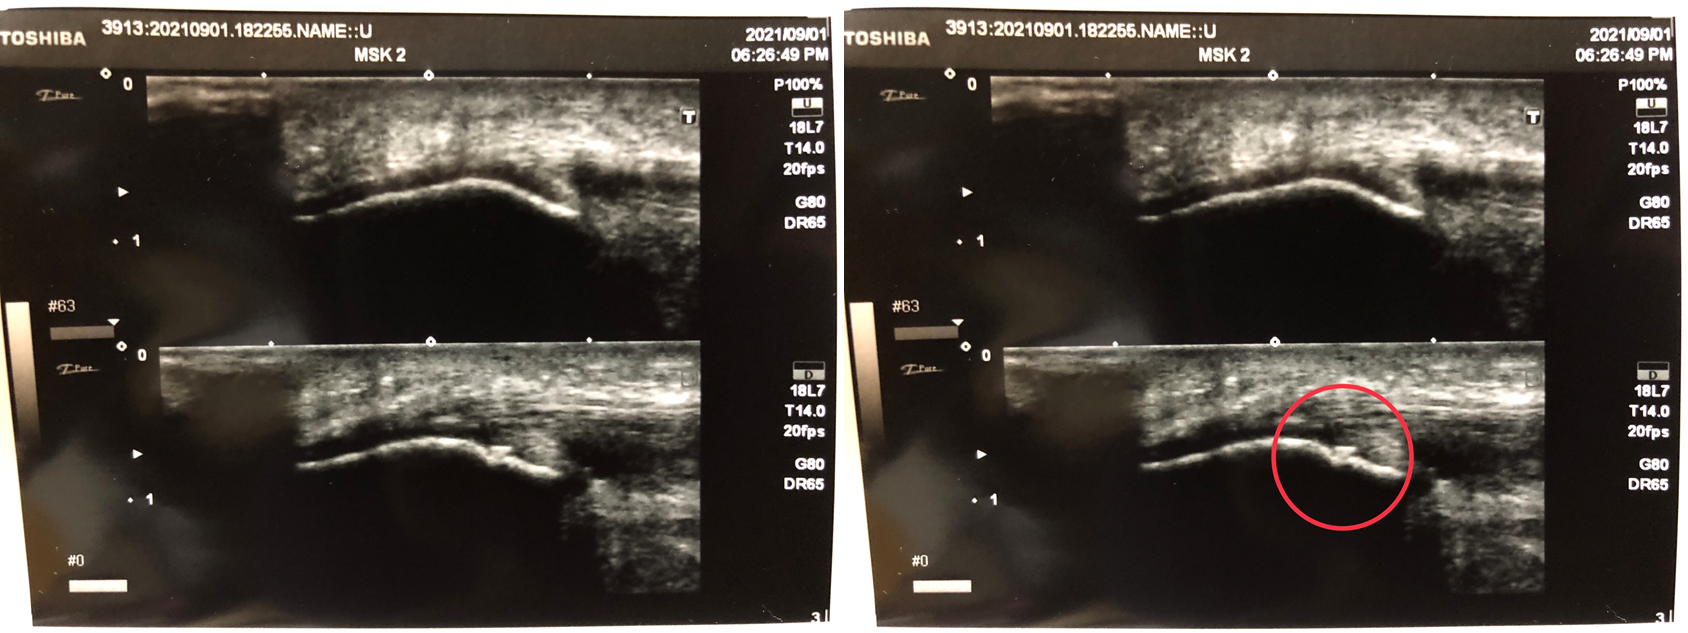

国は、柔道整復師が業務の中で超音波エコー観察機器を使い、損傷の評価や程度を対応の参考情報にすることは、差し支えないと、正式に見解を出している。

もし、骨折や脱臼等の重傷症状の場合は、超音波エコー画像が応急手当への参考情報となる。

※なお、ねんざや、打撲、肉離れ、筋腱の断裂などは、超音波エコー観察検査を実施した上、柔道整復師自身の判断で治療が行えます。